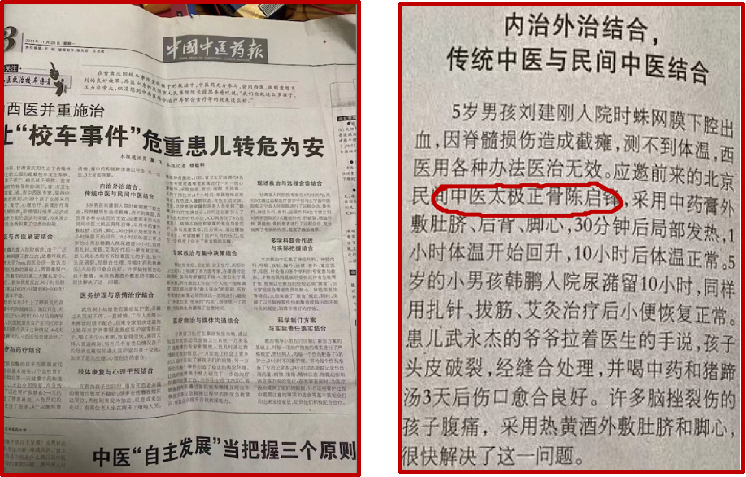

(图片源自网络)

(左一陈启锋,右一刘维忠)

(右一陈启锋调理)

(左一刘维忠,右一陈启锋)